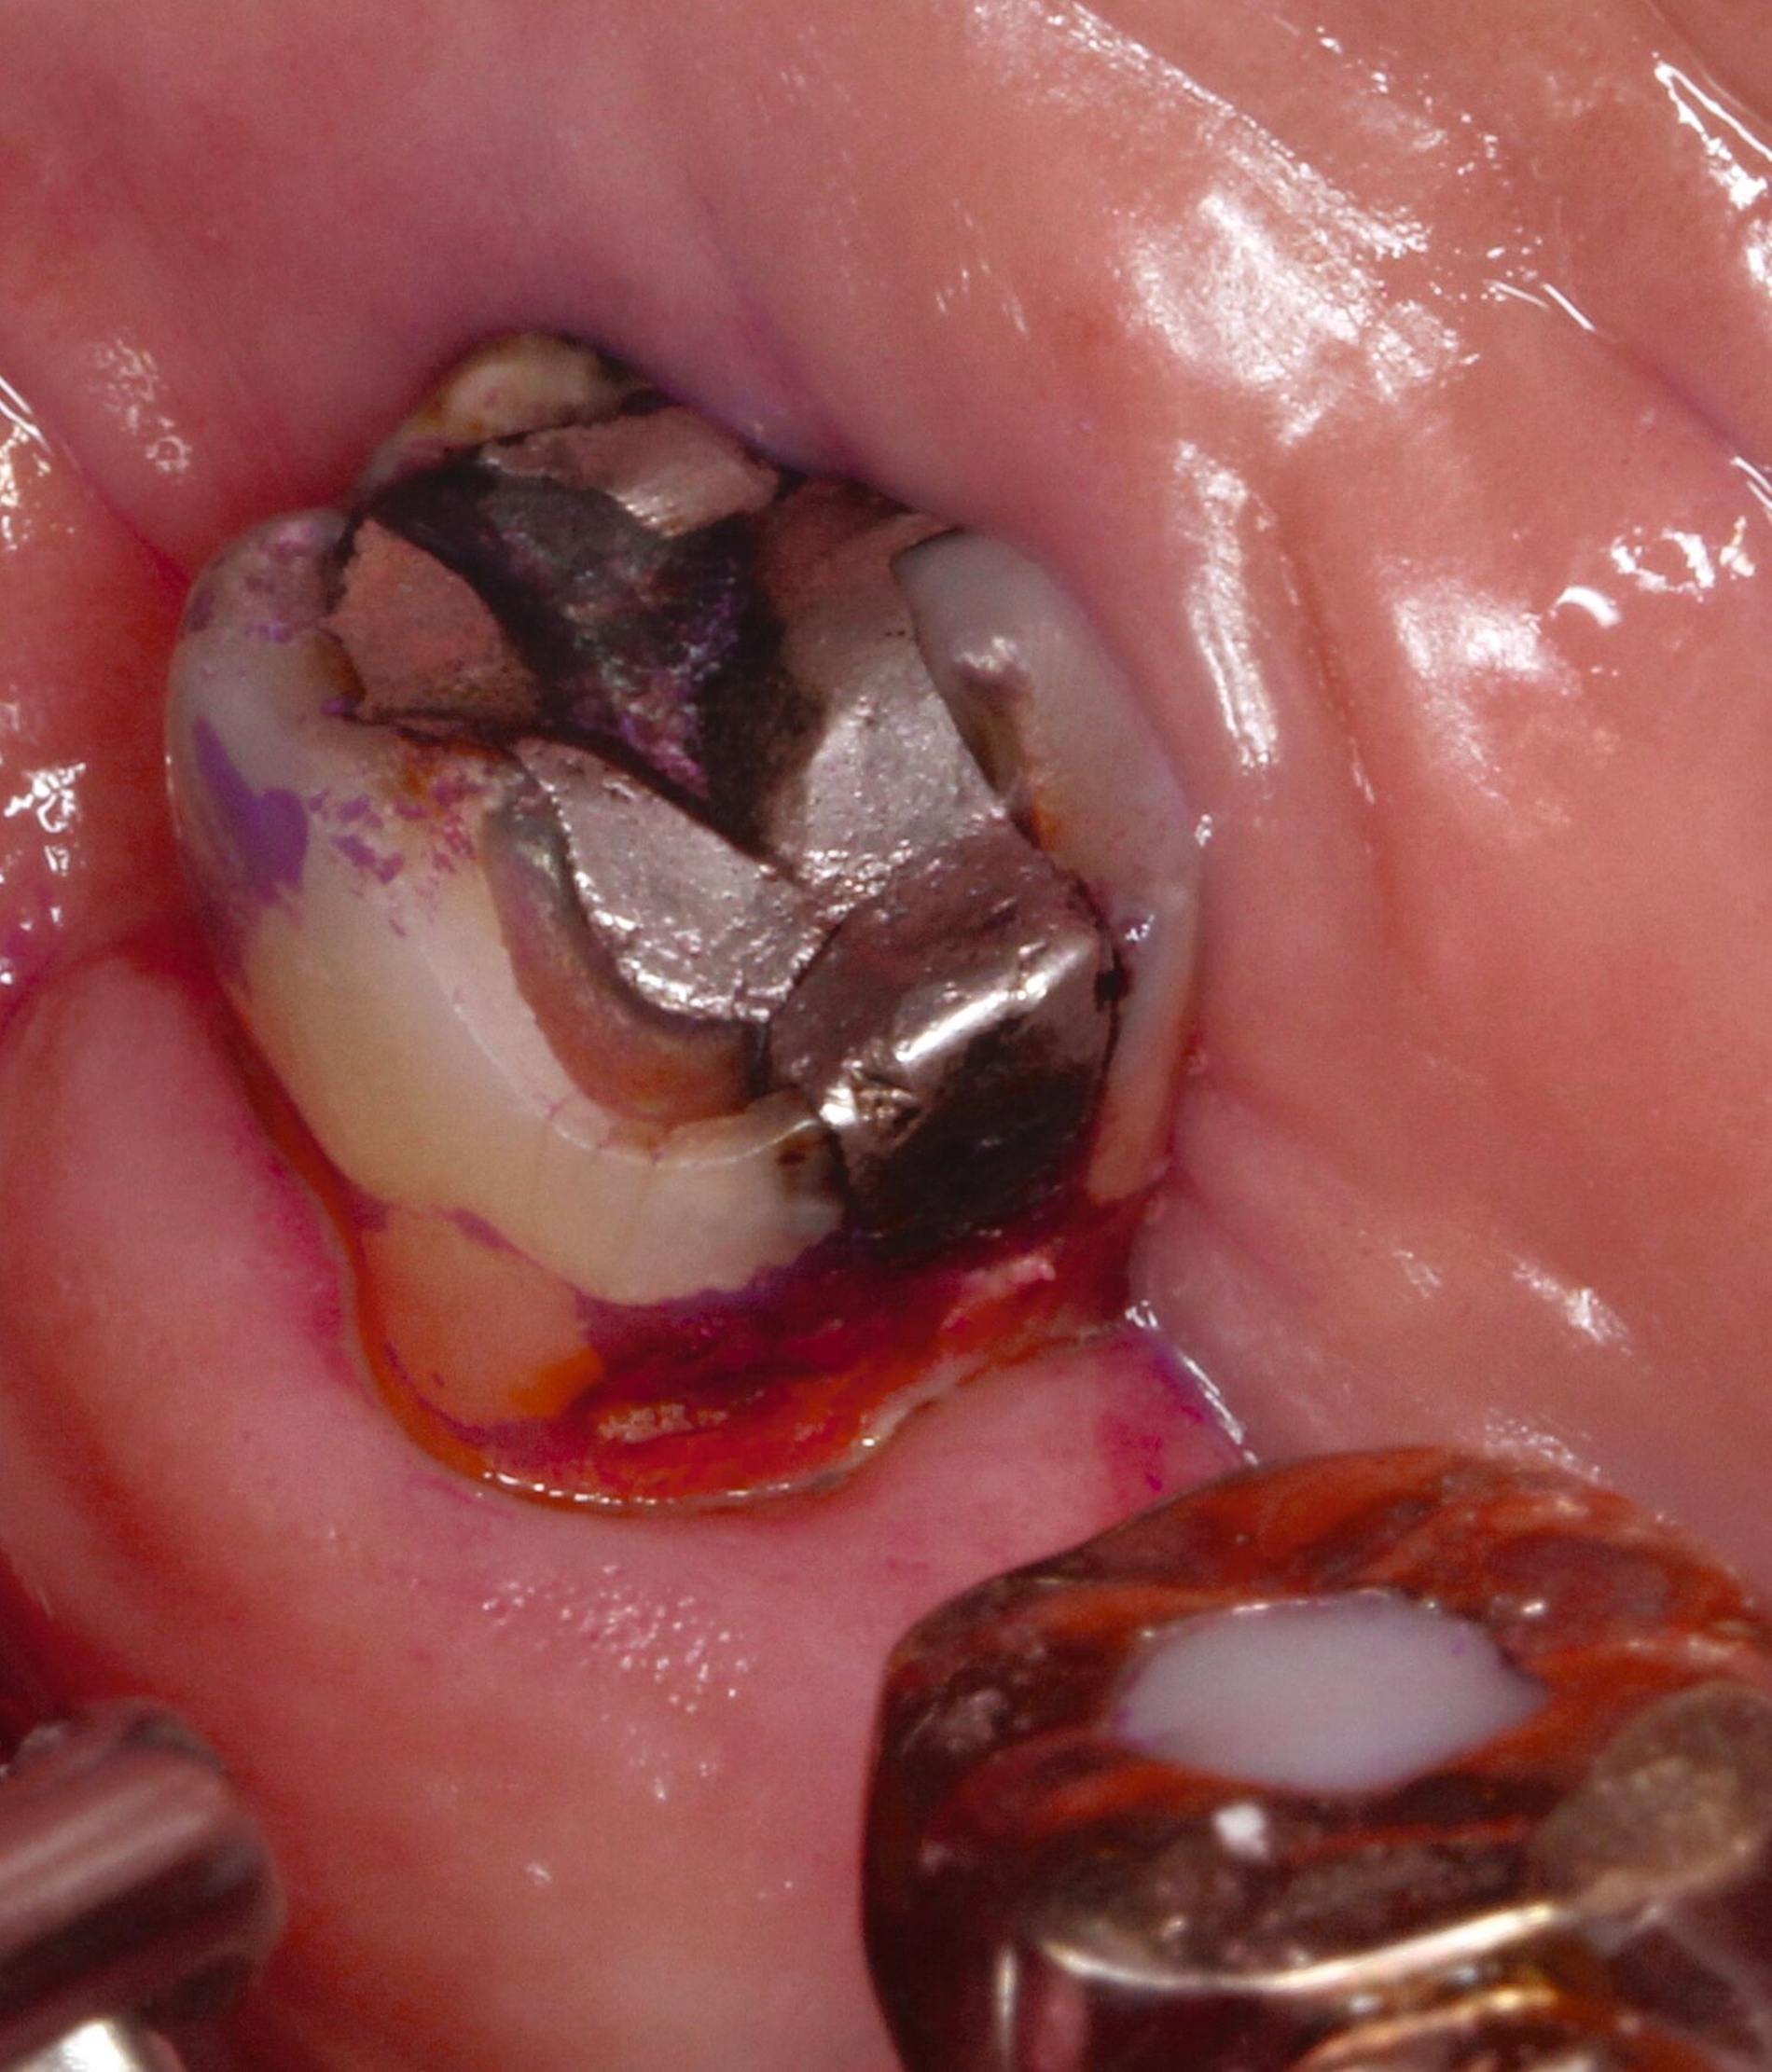

Eine bekannte Nebenwirkung bei Anwendung auf kariösen Läsionen ist die Schwarzfärbung des behandelten Bereichs (Abbildungen 3, 4). Verfärbungen können aber auch bei Applikation auf kariesfreien Wurzeloberflächen entstehen, diese sind jedoch mit einer professionellen Zahnreinigung gut zu entfernen (Abbildung 2).

Der Wirkungsmechanismus ist bislang nicht aufgeklärt. Die wesentlichen Verbindungen in SDF-behandelten Läsionen sind Silberphosphat, Silberoxid und Silbersulfid. Silberphosphat ist ein guter Photokatalysator [Yi et al., 2010], der spezifische chemische Reaktionen mit oder zwischen den verschiedenen beteiligten Verbindungen und Zahnstrukturen induzieren oder aber die auch ohne Licht eintretenden Reaktionen einfach beschleunigen könnte. Es wird vermutet, dass beispielsweise metallische Silbernanopartikel entstehen könnten [Li et al., 2019]. Abbildung 3 zeigt bräunliche Verfärbungen der Schleimhaut nach Lichteinwirkung.